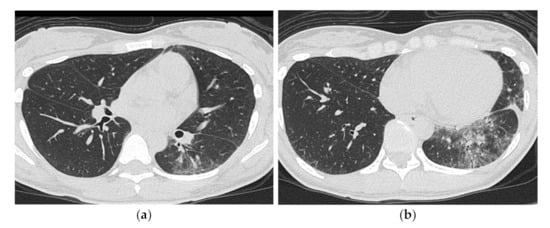

3.2. Anti-MDA5 Antibody (Anti-MDA5 Ab)

HRCT Findings of Patients with Anti-MDA5 Ab

| Chronic to subacute onset >> Acute/rapidly progressive | Acute or subacute onset, often rapidly progressive |

| Distribution along the bronchovascular bundles in the bilateral lower lung fields > diffuse | Diffuse, predominantly in the lower lung fields, or both |

| Reduced volume of the lower lobes | Peribronchovascular lesion of the periphery of lower lobes, with parallel spread to the pleura |

| Reticular shadows or consolidation > GGO | Patchy distribution |

| Good response to treatment but relapses | GGO and consolidation |